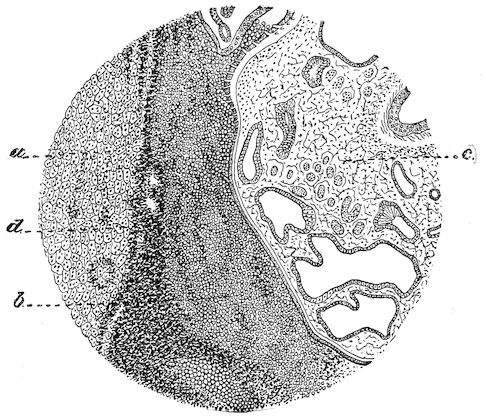

Fig. 8.—Transverse section through the middle region of the face in a pig suffering from osseous cachexia.

18In the final stages, the bones may be cut with a knife, and a time arrives when bony tissue seems completely to have disappeared; thus, as shown in Fig. 8 herewith, it was possible to cut the entire head of a pig into thin slices without the slightest difficulty. All parts of the head had been affected by the softening change.

From the chemical point of view, the diminution in mineral salts and in phosphate of calcium has long been recognised, but the degree of this change varies according to the phase. In human beings the proportions have been estimated as follows: Normal bone, 50 to 80 per cent. of phosphate of calcium; bone in persons suffering from osteomalacia, 5 to 20 per cent. of phosphate of calcium. The changes in the ossein have not been carefully studied. We only know that histologically the ossein becomes fibrillar, and that chemically it no longer retains its normal composition.